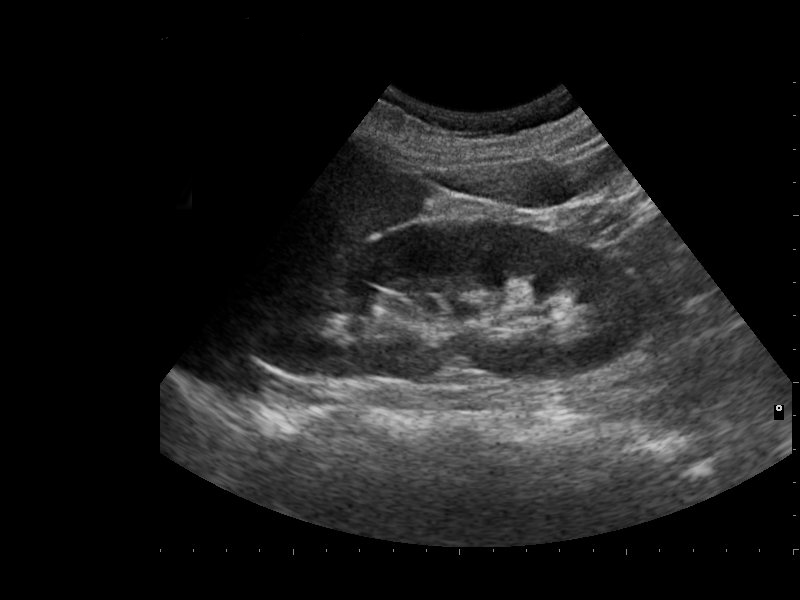

Довольно часто пациенты приходят на прием с целью выполнения ультразвукового исследования почек. Врач УЗД оценивает расположение, форму, размеры, соотношение коркового и мозгового вещества, наличие дополнительных включений и образований, кровоток в режиме ЦДК. Чаще всего больных беспокоят боли в поясничной области и нарушения мочеиспускания. Одной из возможных причин таких жалоб является мочекаменная болезнь. На УЗИ при этом врач видит один или несколько конкрементов в почке или мочеточнике. Камень диагностируется только при размерах более 3 мм и с четкой акустической тенью. Также на узи почек можно увидеть расширение чашечно-лоханочной системы, при выраженных изменениях диагностируется гидронефротическая трансформация или гидронефроз. При этом нарушается отток мочи, что может быть при воспалении почек - пиелонефорите. На УЗИ хорошо визуализируются различные образования почек - кисты, содержащие жидкость и опухоли. Опухоли могут быть доброкачественными и злокачественными, но не всег

Одной из возможных причин таких жалоб является мочекаменная болезнь. На УЗИ при этом врач видит один или несколько конкрементов в почке или мочеточнике. Камень диагностируется только при размерах более 3 мм и с четкой акустической тенью.

Также на узи почек можно увидеть расширение чашечно-лоханочной системы, при выраженных изменениях диагностируется гидронефротическая трансформация или гидронефроз. При этом нарушается отток мочи, что может быть при воспалении почек - пиелонефорите.

На УЗИ хорошо визуализируются различные образования почек - кисты, содержащие жидкость и опухоли. Опухоли могут быть доброкачественными и злокачественными, но не всегда удается определить характер образования, поэтому в таких случаях рекомендуется консультация онкоуролога и КТ почек.